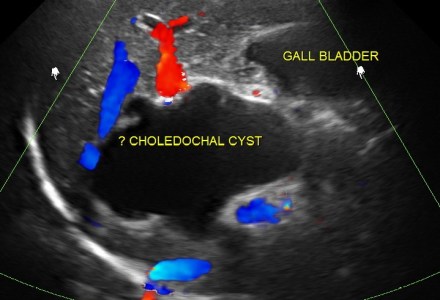

CHOLEDOCHAL CYSTS , CHOLELITHIASIS AND INCIDENTAL BI-CORNUATE UTERUS